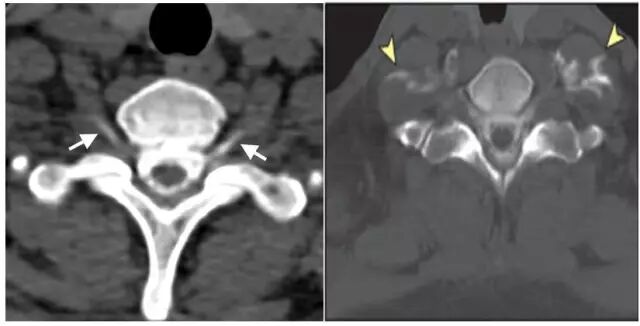

患者,男,40岁;因不明原因反复头痛并加重2月,于2017年4月21日当地医院头颅CT、MRI提示:双侧额颞顶部慢性硬膜下血肿收住院(图1)。并于4月24日行“左侧慢性硬膜下血肿钻孔引流术”。术后患者卧床、静脉补液,头痛症状有所缓解。复查头颅CT显示左侧血肿较前减少,但右侧稍增大(图2)。

图1. 第一次术前CT及MRI显示双侧慢性硬膜下血肿,中线稍右偏。